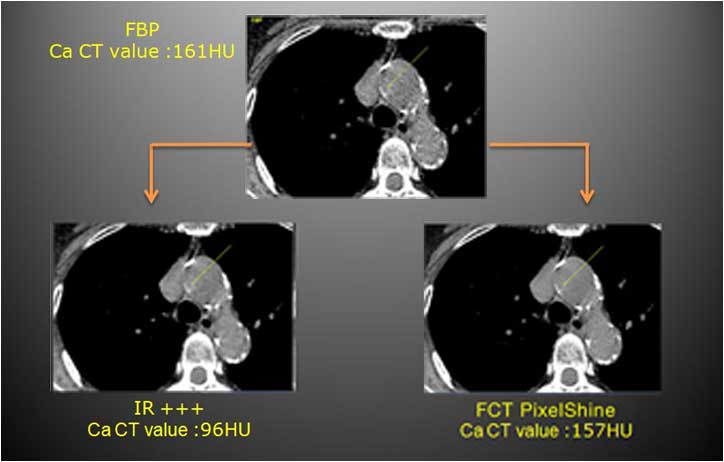

Der CT-Wert wird durch die iterative Rekonstruktion verringert, während FCT PixelShine in der Lage ist, den CT-Wert von kleinen Objekten beizubehalten.